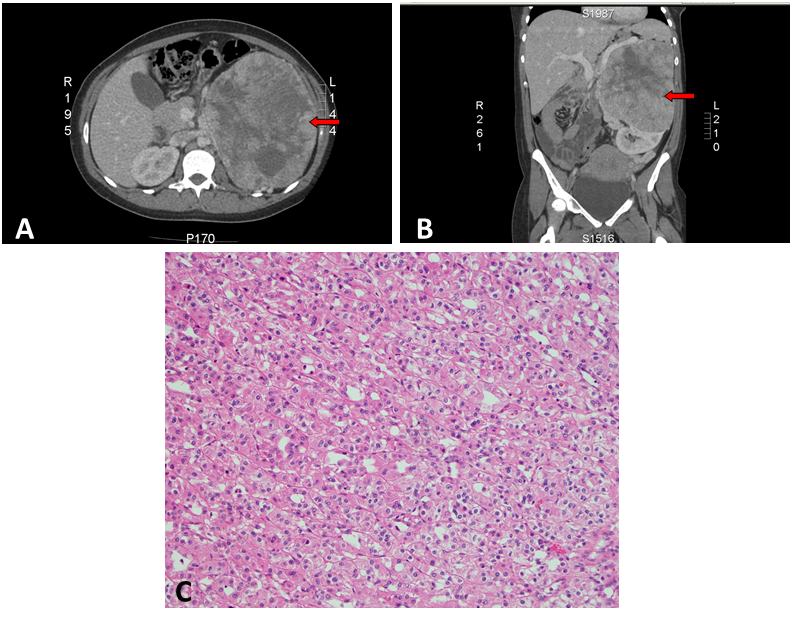

A healthy baby girl was delivered via spontaneous vaginal delivery at term. Within a few days postpartum, an abdominal computed tomography scan revealed a large left heterogeneous mass with mixed density and contrast enhancement and a small indeterminate liver lesion (Figures 1 A and B). Open left radical nephrectomy was performed 3 weeks following delivery. Intra-operatively, there was no evidence of metastatic disease and a 2086g left renal tumor measuring 23.0x17.0x13.0 cm3 was successfully removed. The post-operative recovery was uneventful. Pathological analysis revealed chromophobe RCC, pT2bN0M0 with peri-nuclear halo and transitional cells (Figure 1 C). There was no venous infiltration and the tumor was CK7, CD117 positive and CD10 negative with no sarcomatoid or rhabdoid differentiation. Surgical margins were clear. Magnetic resonance imaging at one week post-operation showed a small liver nodule consistent with focal nodular hyperplasia and no appearance of typical metastasis in the liver (Figure 2). On follow up, the patient remained well with no evidence of recurrence or metastases.

Figure 2. T1 weighted MRI (axial view).

Figure 2: T1 weighted MRI (axial view): Liver lesion consistent with focal nodular hyperplasia (arrow).